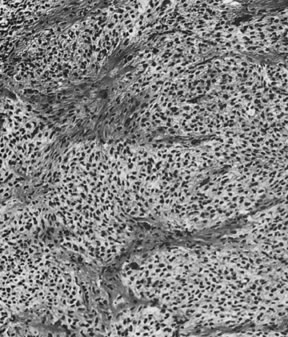

These tumors, which are the most common form of Sertoli-stromal cell tumor, are characterized by immature Sertoli cells, typically containing small oval-to-round nuclei and growing in a variety of patterns, and by a stromal component that varies in its cellularity, most typically being relatively acellular and often edematous, and contains at least some well-differentiated Leydig cells (Fig. 11). A lobular growth is often conspicuous on low power. The Sertoli cells may be disposed in round, oval, or elongated aggregates; in masses or within tubules, but most characteristically, they lie in short, single rows that simulate the sex cords of the developing testis. Varying amounts of lipid may be present in the neoplastic cells. The tumors are usually associated with androgenic manifestations but may be estrogenic or nonfunctioning.

Fig. 11. Sertoli-Leydig cell tumor of intermediate differentiation (magnification, ×240).(Morris JM, Scully RE: Endocrine Pathology of the Ovary. St. Louis, CV Mosby, 1958.)